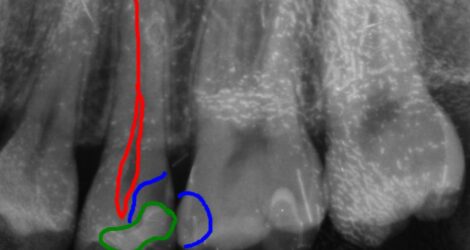

40代男性 上顎第二小臼歯が2次カリエス

口腔内/レントゲン画像

下の部分的なレントゲンになります。

青い部分が虫歯になり、赤色の歯の神経との距離がかなり近くもしくは虫歯で感染が起きている場合があります。痛みなどの症状がなかったため、MTAセメントを使用し神経保護を行なっていきます。